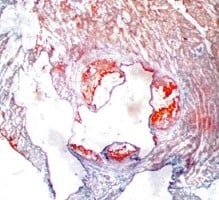

Atherosclerosis Aortic Root Histology Examples

Oil Red-O Staining (fat-soluble dye)